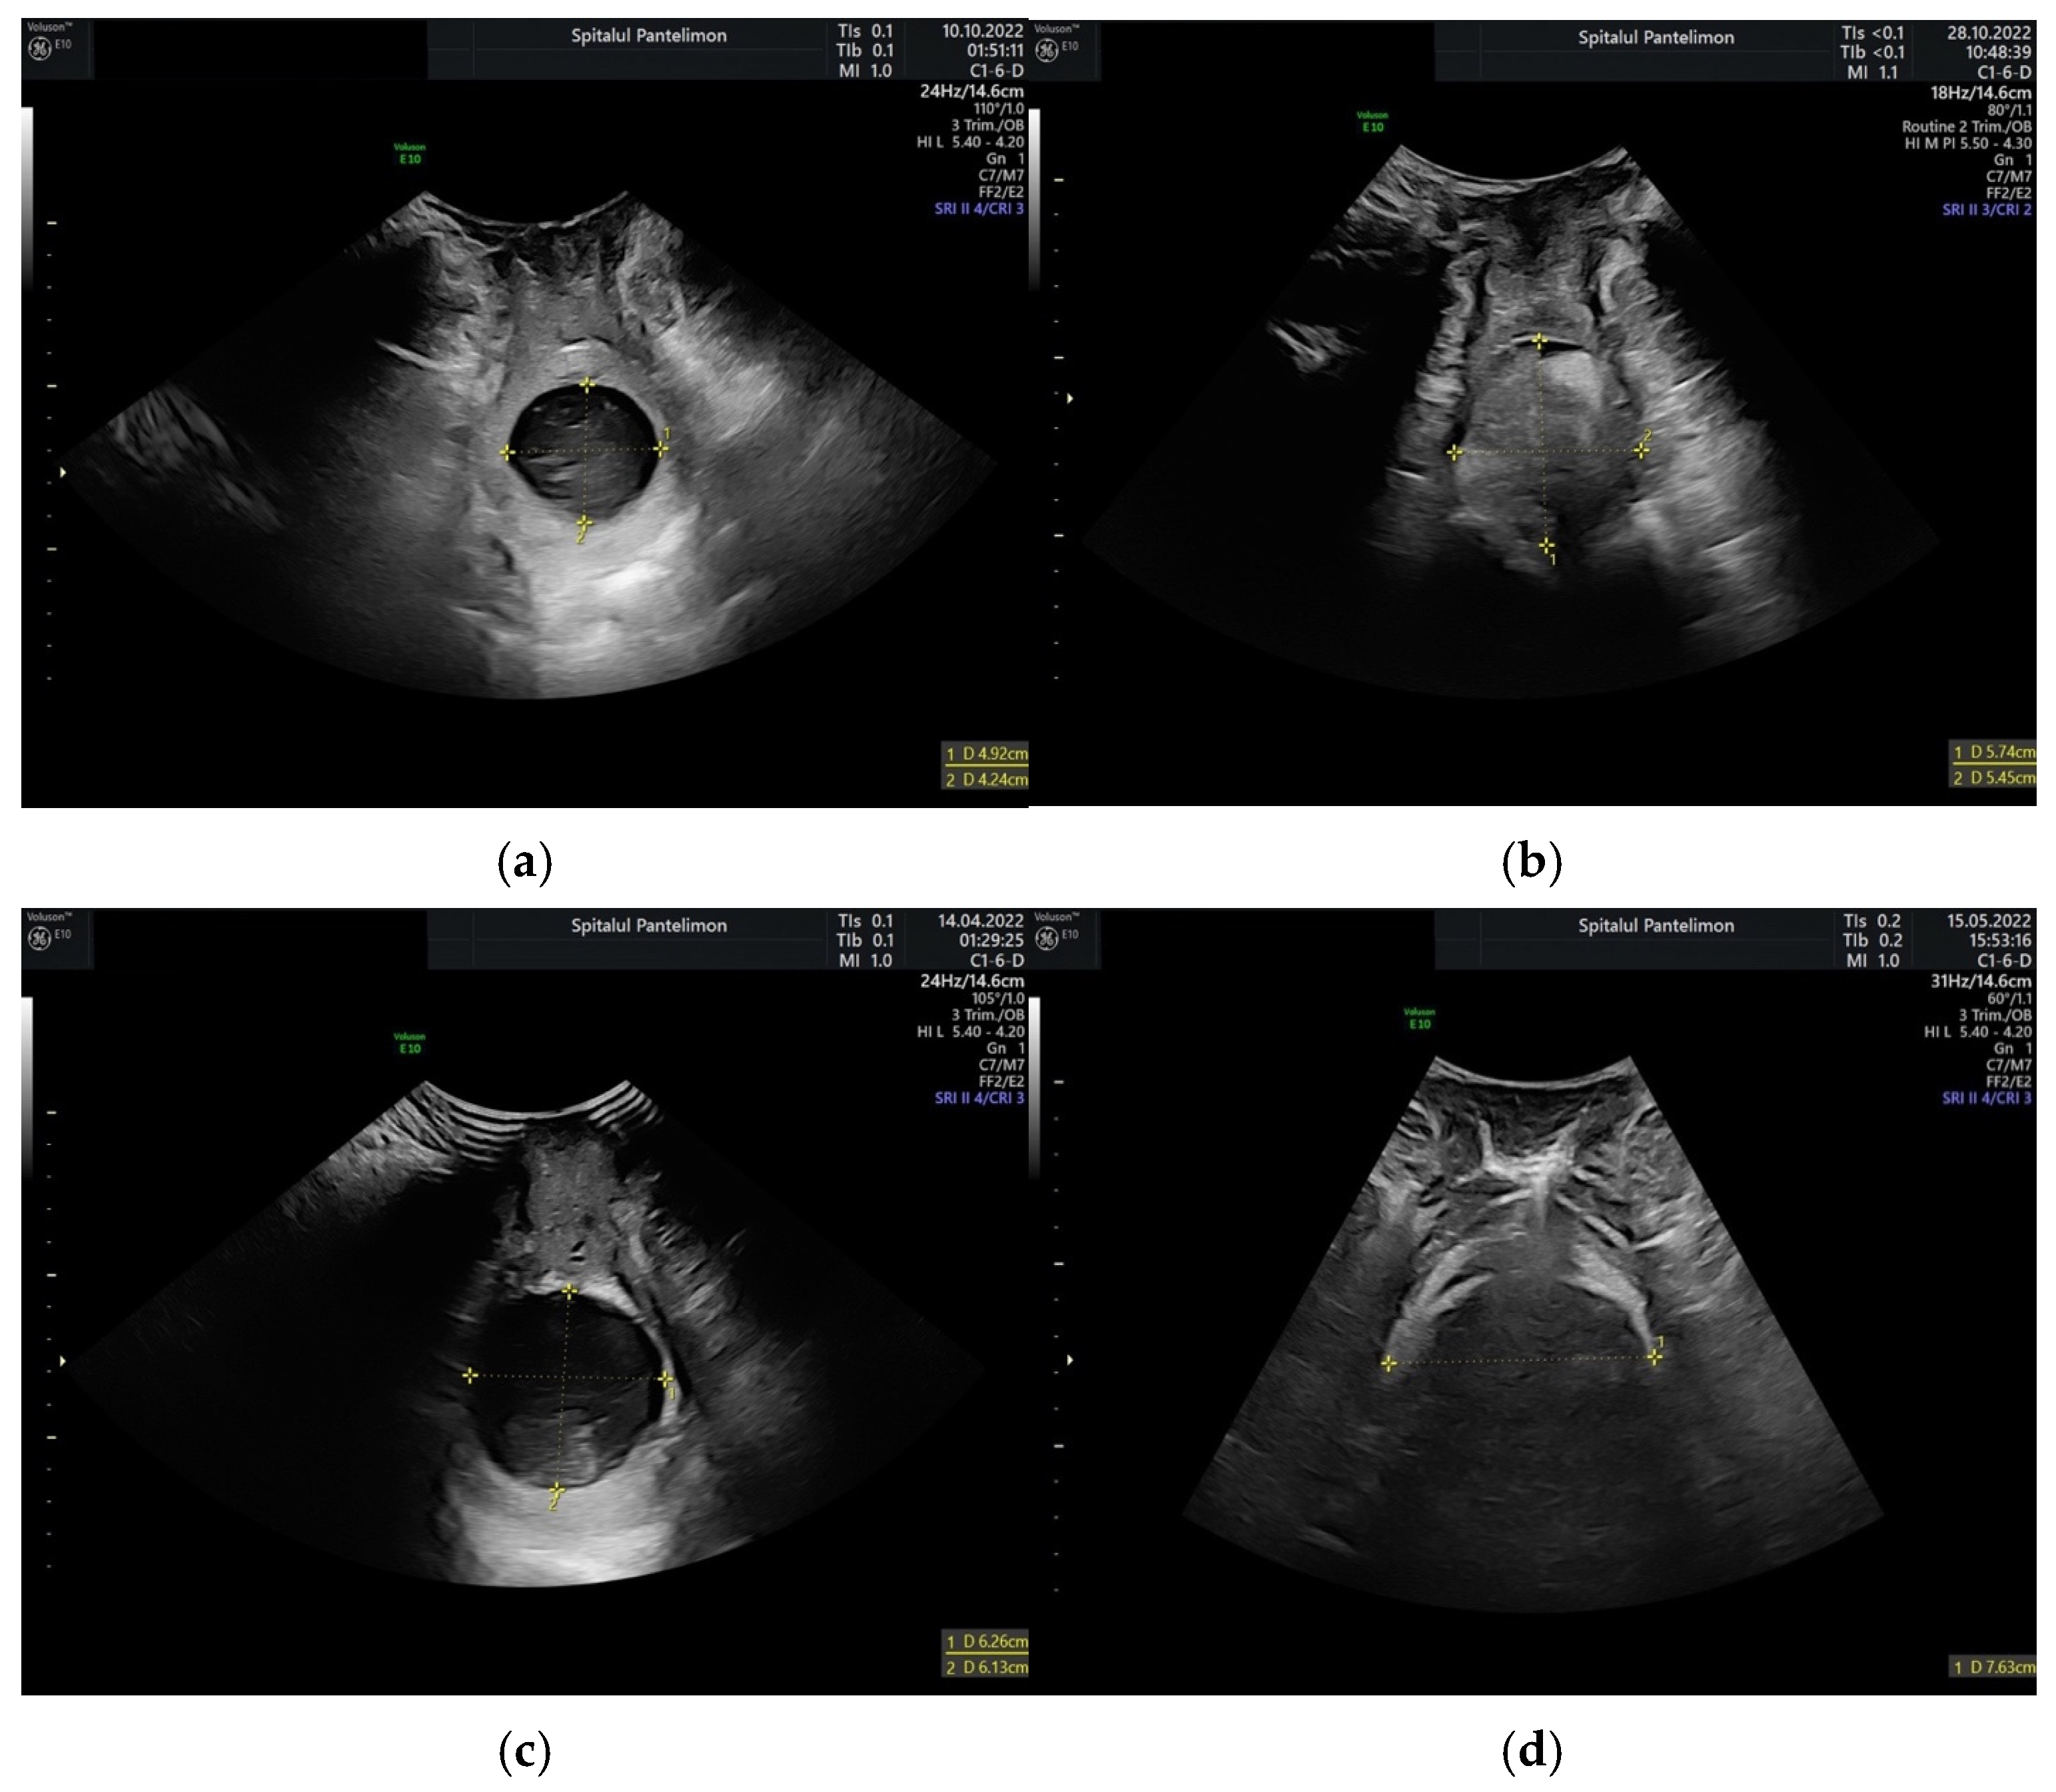

3.2. Ultrasound Measurements

3.3. Membrane Integrity Influence on Ultrasound Parameter Measurement Accuracy